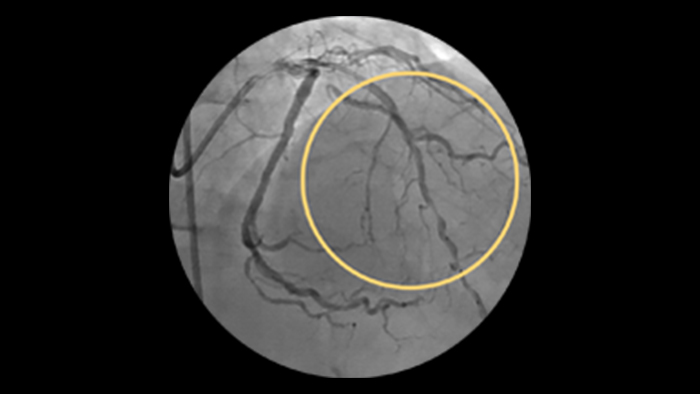

Ostial and bifurcation lesions

Ostial and bifurcation lesions represent nearly 40% of complex PCI’s3